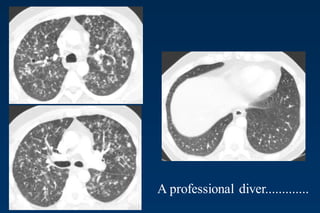

A professional diver.............

.......after cessation of smoking

Differential Diagnosis

Only small nodules

Sarkoidosis, Silikosis

Only cysts

idiopathic Fibrosis

LAM

Destruktive emphysema